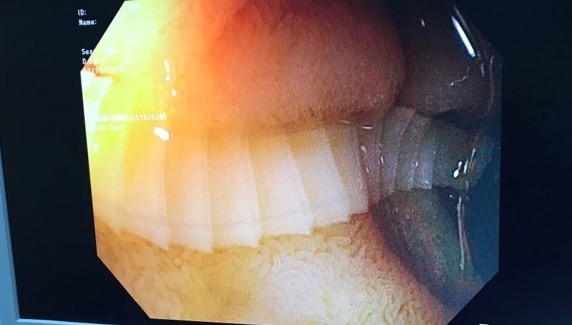

Trước đó, bệnh nhân đến BV Chợ Rẫy để khám bệnh và nội soi tiêu hóa. Khi nội soi, bác sĩ nhận thấy trong tá tràng bệnh nhân có một con sán dây bò. Bác sĩ kéo con sán ra nhưng đầu sán bám rất chắc nên chỉ kéo được giữa chừng. Do đó, bệnh nhân được dùng thuốc sổ giun để tiếp tục đẩy con sán ra ngoài.

Hình ảnh nội soi con sán dây bò dài 1m sống trong tá tràng bệnh nhân. Ảnh: BVCC

Bác sĩ Tăng Trung Hiếu - Khoa Nội soi (BV Chợ Rẫy), cho biết sán dây bò trưởng thành có thể dài từ 2-4 m, thân có khoảng 800-1.000 đốt sán trắng dẹt.

Sán dây bò thường ký sinh ở ruột non nên hấp thu hết các chất dinh dưỡng, khiến bệnh nhân bị suy dinh dưỡng, rối loạn tiêu hóa, đau bụng, thiếu máu kéo dài. Bác sĩ khuyến cáo người dân nên ăn chín, uống sôi và dùng thực phẩm có nguồn gốc rõ ràng.